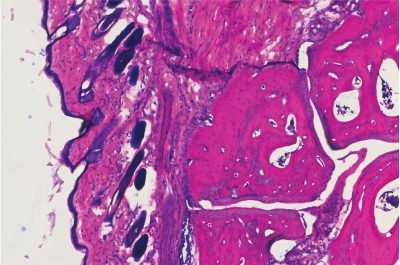

NVG-2089 anticorpo-immagine: un’istologia che mostra l’articolazione della caviglia di un topo quattro giorni dopo aver ricevuto il nuovo trattamento anticorpale, V11 sFc. Crediti: laboratorio Ravetch, Rockefeller University

Successivamente, hanno ingegnerizzato una IgG espressa in modo ricombinante per potenziare il legame con questi recettori e l’hanno infusa in topi con recettori Fc umani in cui era stata indotta l’artrite (ovvero iniettata con siero isolato da un topo con artrite spontanea). Un gruppo simile di topi artritici è stato trattato con l’infusione convenzionale di IVIG.

Entrambi i gruppi hanno tratto beneficio dall’infusione, riscontrando una riduzione del gonfiore articolare. Tuttavia, le dosi erano notevolmente diverse: per ottenere lo stesso effetto di una dose della nuova molecola, è stata necessaria una dose 100 volte superiore di IVIG.